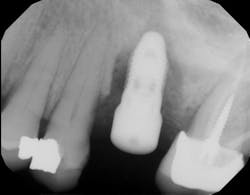

One recent retrospective clinical study investigated the correlation between low serum levels of vitamin D and early dental implant failure. This study evaluated 885 patients who had been treated with 1,740 fixtures. Patients with vitamin D deficiency (serum levels of vitamin D <10 ng/mL) showed an early implant failure rate of 11.1%, compared to a failure rate of 2.9% in patients with normal levels of the vitamin (>30 ng/mL).8 The authors concluded that in cases of unknown failure, serum levels of vitamin D should be examined, and the operator may be advised to administer vitamin D weeks to months prior to implant surgery (figures 3 and 4).